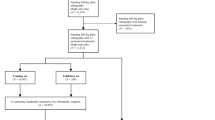

The AI was trained on over 15,000 radiographs to measure various clinical angles and lengths from LLRs. We performed a retrospective single-center analysis on 295 LLRs obtained between 2015 and 2020 from male and female patients over 18 years. AI and expert measurements were performed independently. Kellgren-Lawrence score and reading time were assessed. All measurements were compared and non-inferiority, mean-absolute-deviation (sMAD), and intra-class-correlation (ICC) were calculated.